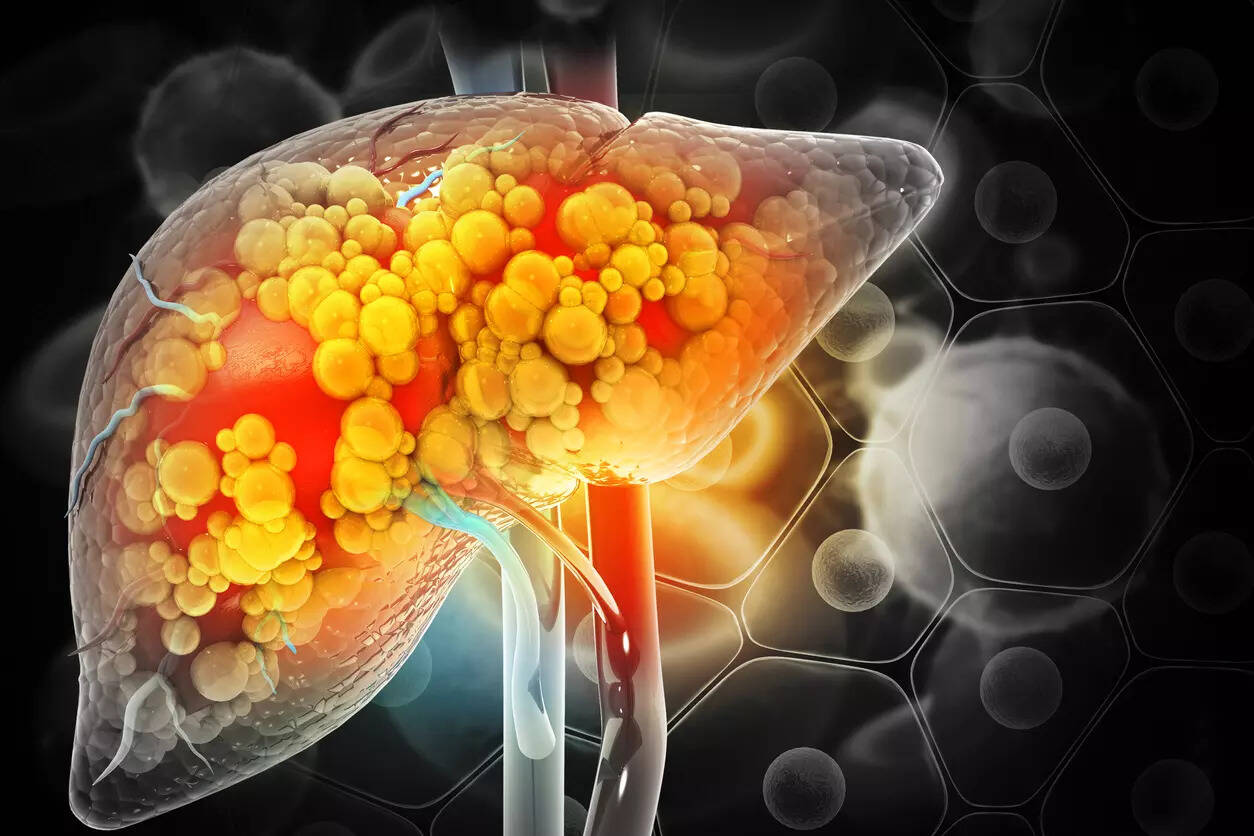

The liver is essential: humans need it to live. The liver contributes to metabolism and food storage, produces proteins that help with blood clotting and plays a vital role in the immune system.

At the cellular level, alcohol is a toxic substance that is metabolized (broken down) primarily in the liver. When the dose of alcohol is too high, liver cells become inflamed and damaged (liver inflammation is called hepatitis).

Over time, inflamed or damaged cells are replaced by fibrosis, which is the replacement of normal liver tissue with scar tissue, resulting in cirrhosis, or severe scarring and liver dysfunction. Cirrhosis can be fatal on its own and can also lead to liver cancer.

Liver disease caused by alcohol is referred to as alcohol-related liver disease or ALD, previously called alcoholic liver disease. The heaviest drinkers, often those who have alcohol use disorder (AUD), can develop cirrhosis and liver failure.

But alcohol isn’t the only key contributor to the rise in deaths from liver disease. Another is the rise of a condition called metabolic dysfunction-associated steatotic liver disease, or MASLD.

Despite the complicated name, MASLD is a type of liver disease that is caused by the same metabolic disturbances that have accompanied the rise of overweight and obesity coupled with inadequate physical activity. This is the same set of risk factors that have led to the increase in diabetes. So one can conceive of MASLD as the liver equivalent of diabetes.